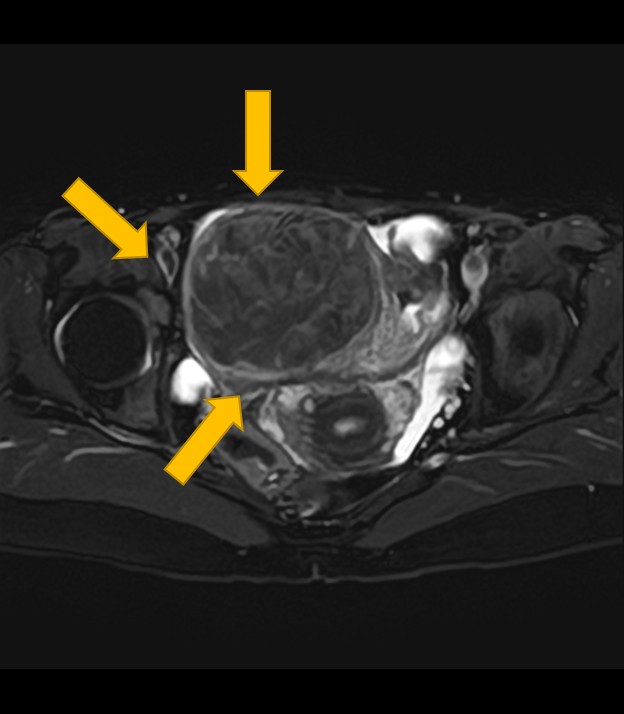

2. 卵巣腫瘍(嚢腫)のMRI:良性・悪性を判断する「中身」と「充実部分」の評価

卵巣嚢腫の中身が液体、脂肪、血液など何であるか、嚢腫壁の性状(肥厚、隔壁の有無)、充実部分の有無や血流を評価することで、良性か悪性(がん)かの可能性を判断する重要な手がかりとなります。

3. 子宮内膜症・腺筋症のMRI:病変の広がりと周囲臓器への浸潤・癒着を把握

卵巣にできるチョコレート嚢胞の内部性状や、子宮腺筋症の広がり、さらに深部子宮内膜症による周囲臓器(腸管、膀胱など)への浸潤や癒着の程度まで詳細に把握できます。